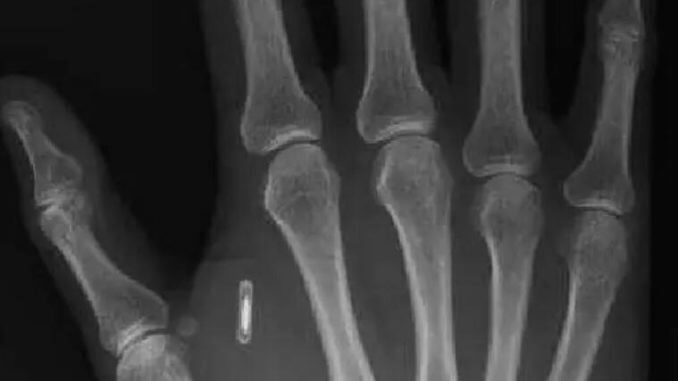

Sui chip sottocutanei c’è molta letteratura che ha analizzato le innumerevoli e diverse casistiche relative allo sviluppo dei chip nel campo della medicina, nella quale possono essere già utilizzati come dispositivi medici che incorporano sostanze chimiche (o principi attivi), fungendo quindi da “serbatoi” capaci di rilasciare dosi su richiesta nell’organismo umano. Ed è proprio questo uno degli utilizzi che può meglio rappresentare (positivamente) agli occhi delle istituzioni questi strumenti, e non certo la loro funzione – anche se ugualmente utile – di immagazzinare informazioni e data non perché meno importanti perché calamita di troppe e non sempre meritate critiche. Al momento, già per alcune specifiche patologie (si pensi al caso del pacemaker nella fibrillazione atriale), è previsto l’utilizzo di queste tecnologie ma i progressi scientifici e della ricerca puntano ad un utilizzo più ampio e di “largo consumo”.